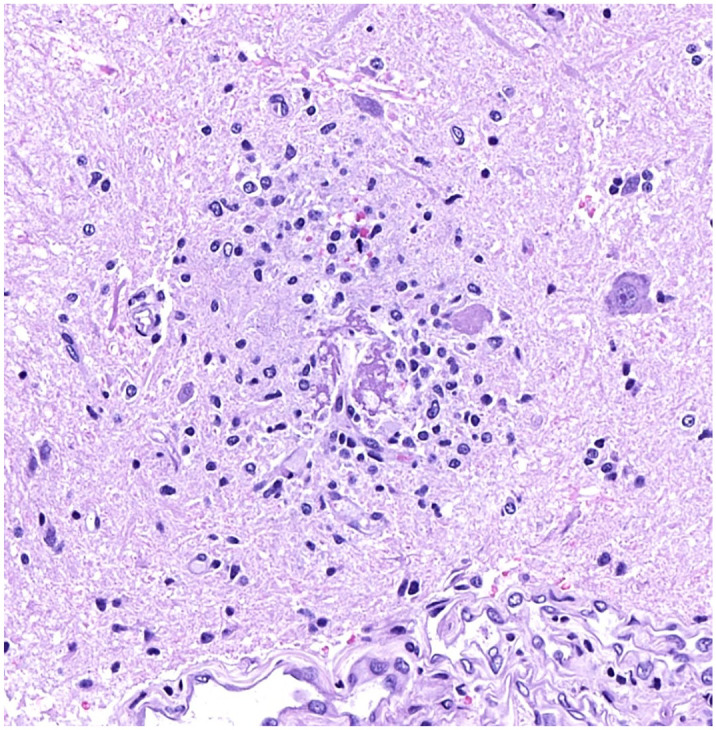

环状出血是中枢神经系统(CNS)周围小血管实质的特征性环状病变,通常发生在脑白质。在人类中,它们出现在各种疾病中,包括恶性贫血、脑脂肪栓塞和脑疟疾。在动物的中枢神经系统中也偶见环状出血,以前在4种患有各种形式贫血的非人灵长类动物(NHP)中有过报道。在这里,我们介绍了4项临床前毒性研究的结果,这些研究测试了4种候选药物在NHPs(食蟹猴)中不同的模式、靶点、作用机制和适应症。在每项研究中,在受影响的动物中观察到环状出血与严重贫血有关,并且与先前报道的一致。它们发生在大脑和脊髓的灰质,偶尔也发生在白质;在大脑中,丘脑、基底神经节和小脑受到的影响尤为严重。病变包括一个中央嗜酸性核心,有时在中心有小血管或嗜酸性到轻微嗜碱性的无定形物质,周围有红细胞和/或小胶质细胞或小胶质细胞聚集体。纤维蛋白染色证实纤维蛋白存在于中心核。在贫血类型/原因上没有发现共性;在一项研究中,贫血被认为是自发的(与治疗无关的)发现。因此,建议在动物出现贫血情况时对大脑进行彻底检查。病理学家在评估与疾病或候选药物的关联时,应该意识到这一发现及其与贫血的关系。

Ring hemorrhages are characteristic ring-shaped lesions in the parenchyma of the central nervous system (CNS) surrounding small blood vessels and are typically reported to occur in white matter of the brain. In humans, they are seen in various diseases, including pernicious anemia, cerebral fat embolism, and cerebral malaria. Ring hemorrhages are also sporadically seen in the CNS of animals and have been previously reported in 4 nonhuman primate (NHP) species with various forms of anemia. Here we present the results of 4 preclinical toxicity studies testing 4 drug candidates of different modalities, targets, mechanisms of action, and indications in NHPs (cynomolgus monkeys). Within each study, ring hemorrhages were observed associated with severe anemia in affected animals and were in line with those previously reported. They occurred in gray matter and occasionally white matter of the brain and spinal cord; in the brain, the thalamus, basal ganglia, and cerebellum were particularly affected. Lesions comprised a central eosinophilic core, sometimes with small blood vessels or eosinophilic to slightly basophilic amorphous material in the center, surrounded by red blood cells and/or microglial cells or microglia aggregates. Fibrin staining confirmed the presence of fibrin in the central core. No commonality in type/cause of anemia was noted; in one study, the anemia was considered a spontaneous (non-treatment-related) finding. A thorough examination of the brain is therefore recommended in the presence of anemic conditions in animals. Pathologists should be aware of this finding and its relationship with anemia when assessing associations with diseases or drug candidates.